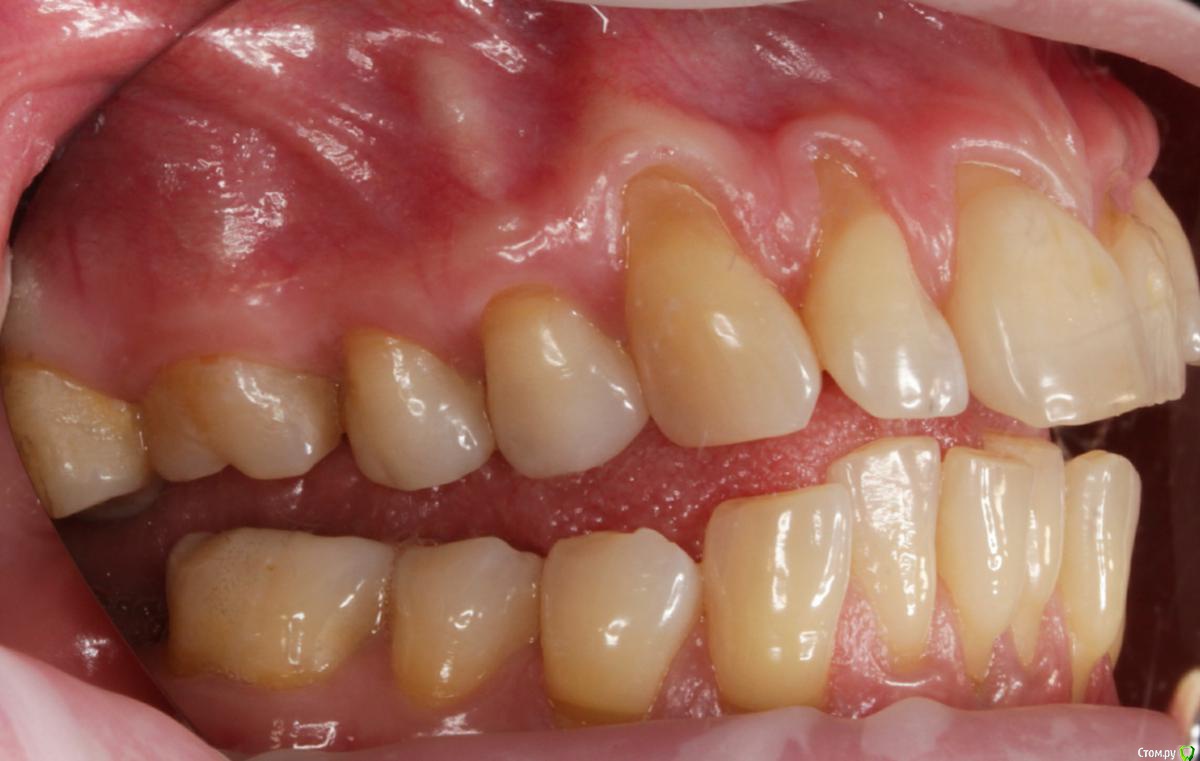

Dmitry DK Опубликовано 31 августа, 2019 Поделиться Опубликовано 31 августа, 2019 Доброго дня! Первичное обращение пациентки было связано с отсутствием 25 зуба, эстетические нарушения слизистой, клиновидные деф-ты в области других зубов - не смущали.В итоге решили, раз проводим операцию ( импл + ССТ ), закроем попутно и рец на верхней челюсти.Реставрацию на 21 зуб все не ставит... Приятных тебе выходных! ) Пациентка проходила лечение 2,5 года назад, пришла на проф осмотр 7 Ссылка на комментарий

Dmitry DK Опубликовано 2 сентября, 2019 Автор Поделиться Опубликовано 2 сентября, 2019 ничего себе попутно, в итоге на имплант 15 минут, а на рецессии 2 часа?))У меня те же мысли были), но согласитесь, что если бы мы этого не сделали - разница в зенитах былабы слишком велика Ссылка на комментарий